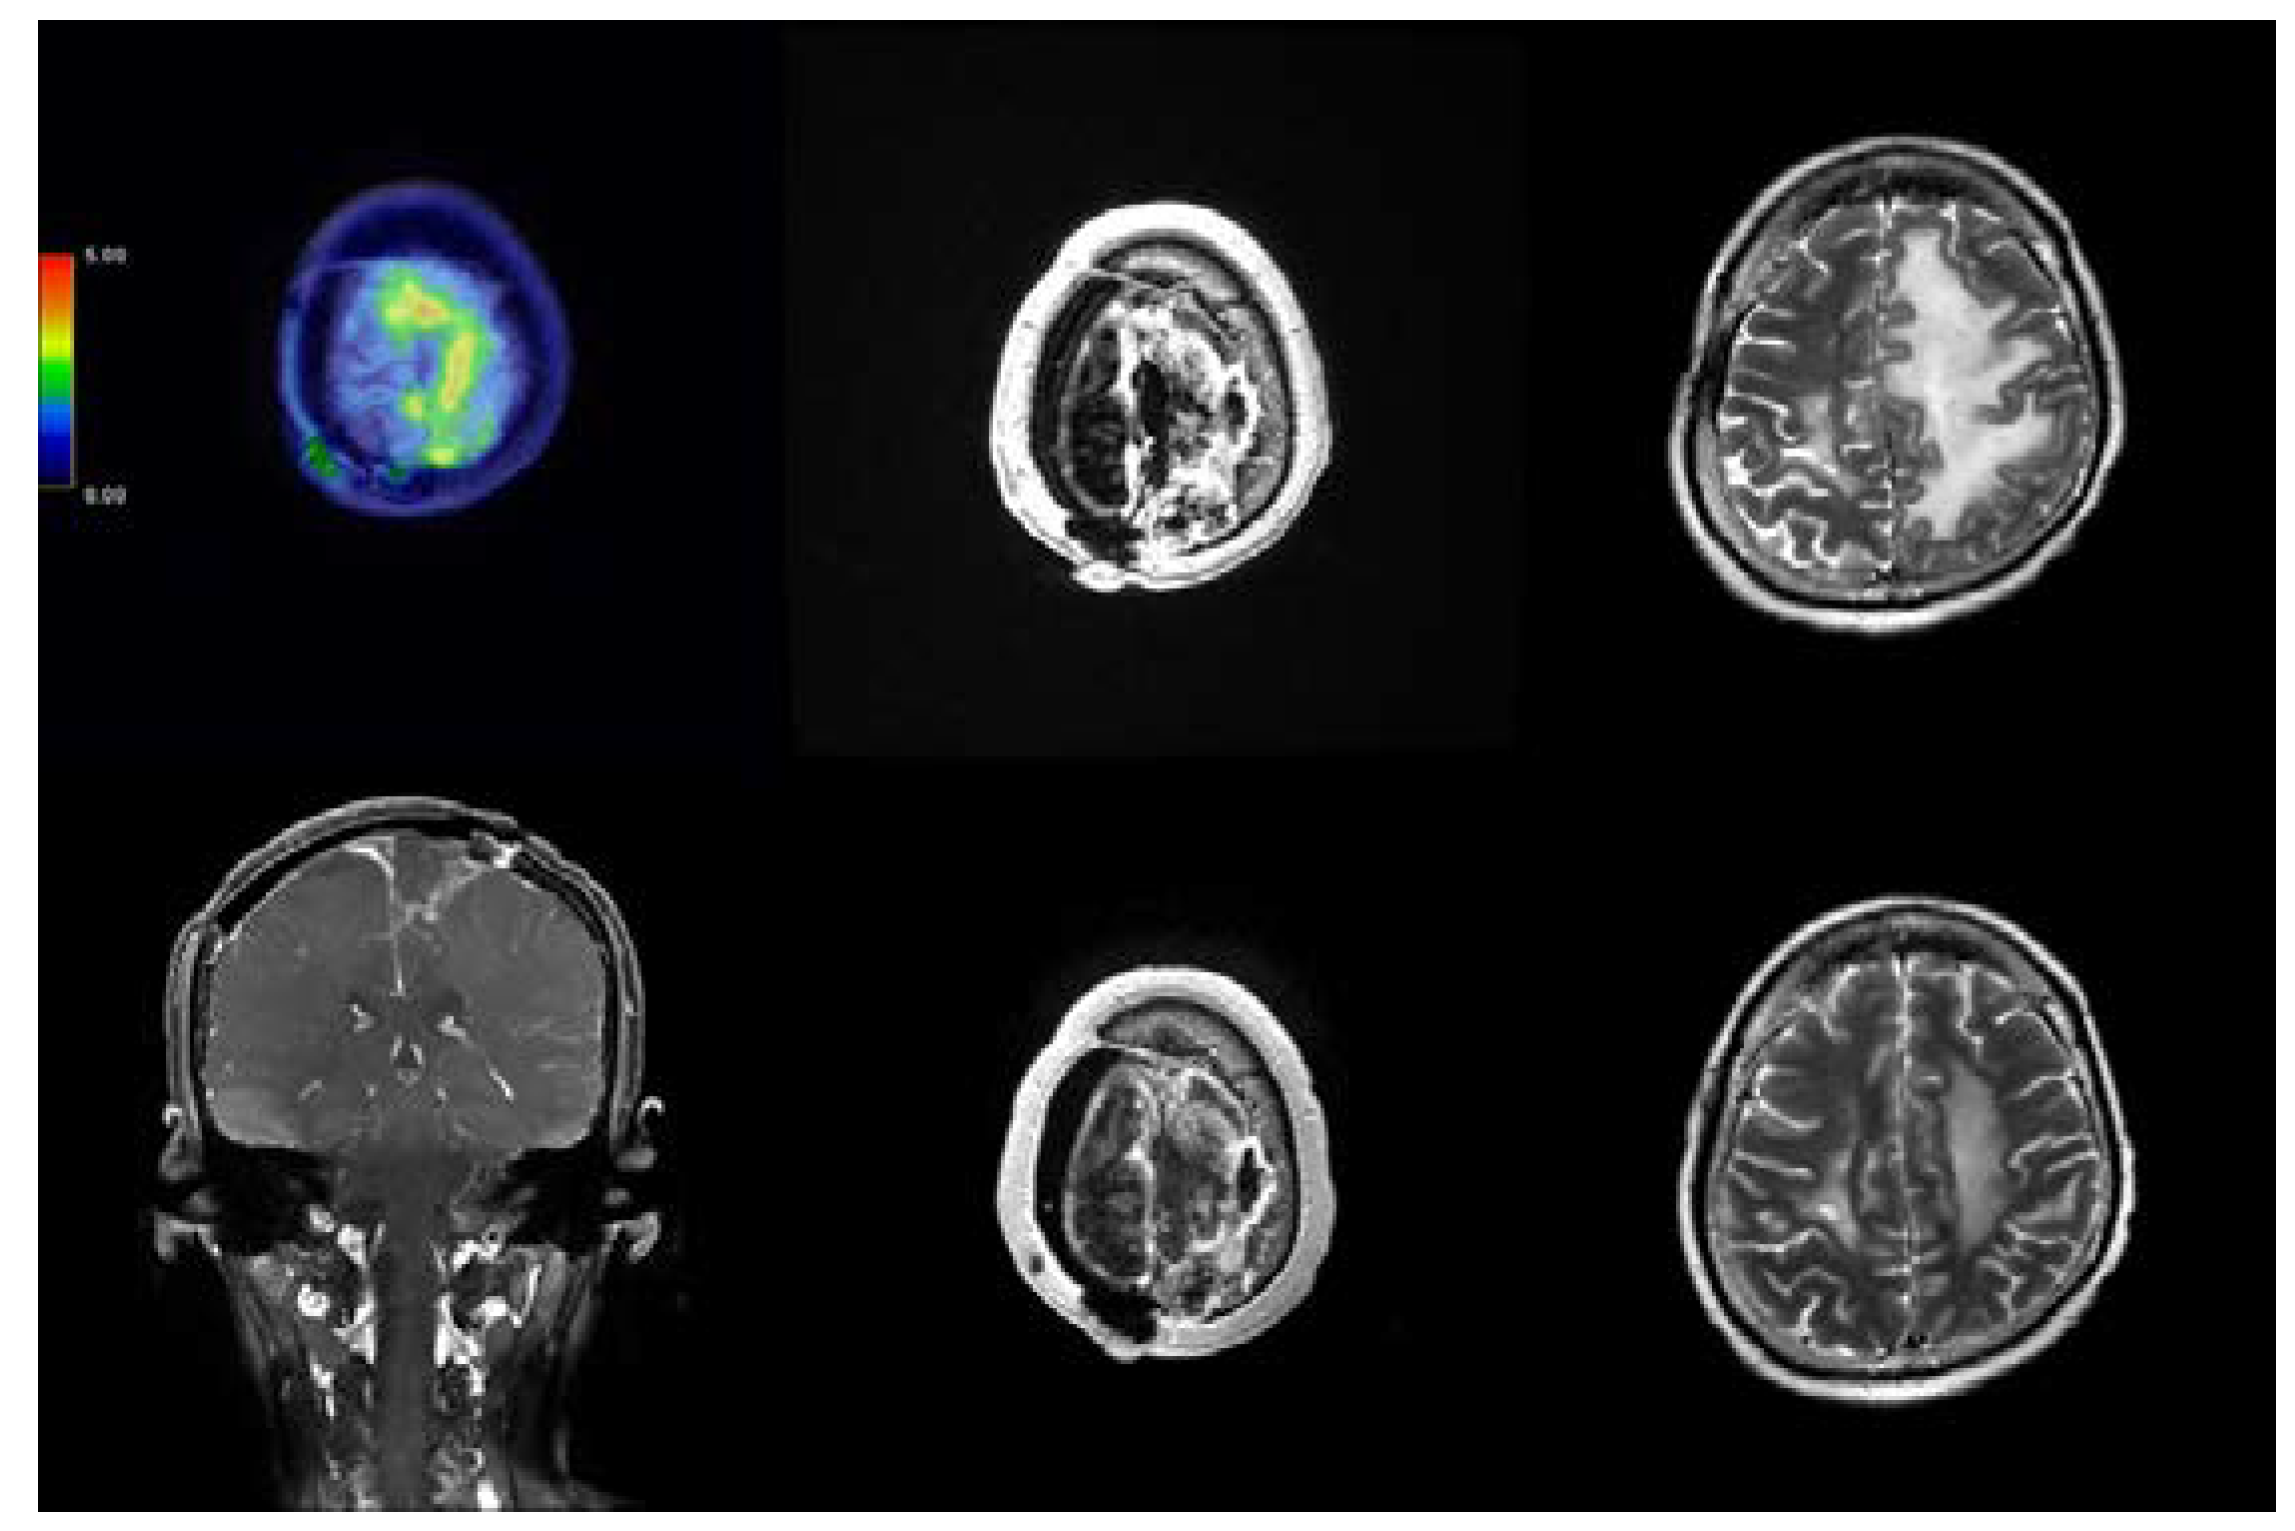

2.1. Case 115

2.2. Case 191

2.3. Case 197

2.4. Case 284